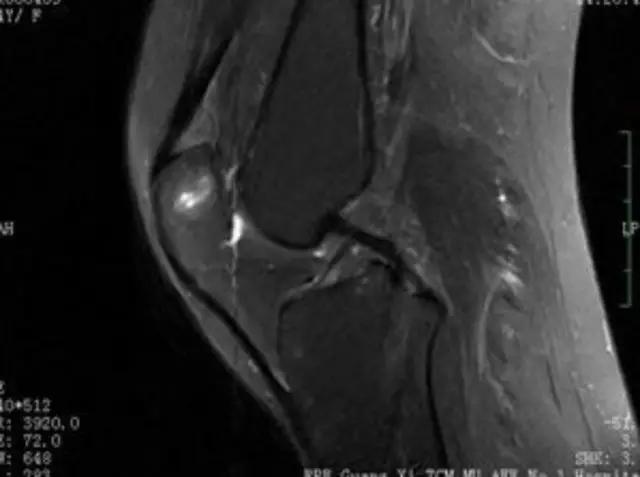

下图是同一个病人的MRI照片,MRI显示的内容更多,包括骨与软策划等,很多早期的、细微的病变都能清晰显示,其诊断报告对病人导致的影响也更大!

我们可能都不熟悉T1、T2,怎么办?当我们发现有问题后,利用照片上图像的对比,推测病变的可能也是一种诊断方法。病例:黄XX,女,39岁,左膝关节反复交锁1年。图1:肿物信号与骨信号一样图2:肿物信号与骨信号一样图3:肿物信号与骨信号不一样 肿物应该与骨相关,但不是骨性,推断:膝关节滑膜软骨瘤。手术后得到证实。